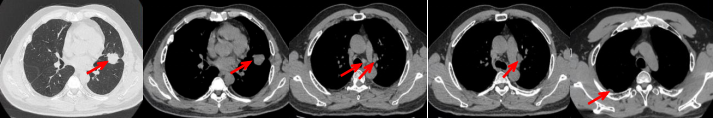

53岁男性,无吸烟饮酒史,脑血栓病史。2024年7月胸部CT:右肺下叶见一团块状软组织密度影,范围约10.8×9.0cm,边界不清,周围并见斑片状磨玻璃密度影,右肺下叶前底段支气管阻塞。纵隔及右肺门见肿大淋巴结影。考虑右肺下叶支气管肺癌。伴纵隔及右肺门淋巴结转移瘤,右下肺静脉瘤栓。2024.7.23行肺穿刺取病理:(肺)腺癌伴有神经内分泌分化。NGS基因检测:RET KIF5B exon15-RET exon12融合。PD-L1(克隆号28-8)TPS=90%。

临床诊断:右肺下叶恶性肿瘤cT4N2aM1a IVA期,肺门淋巴结继发恶性肿瘤,纵隔淋巴结继发恶性肿瘤,胸腔积液,大脑中动脉取栓术后。

治疗经过:2024.08开始口服赛普替尼(160mg,bid)。2024.09复查胸CT评效PR。2025.1复查胸CT:右肺下叶外基底段见一不规则形实性肿块,大小约94mm×87mm,边缘呈分叶状,其内密度不匀。右侧胸腔见少许水样密度影。评效PD,PFS=5个月。患者未同意再次组织活检,目前应用卡博替尼治疗,仍在随访中。治疗期间未出现毒性反应。

55岁男性,无吸烟史,有饮酒嗜好。2024年11月常规体检胸CT:左肺上叶占位性病变,大小约2.7×2.4cm,恶性可能大;左肺、左侧叶间胸膜及胸膜下多发微小结节,转移待除外。左侧胸腔积液,部分骨质改变。2024年12月初肺穿刺活检,病理:(肺)腺癌。NGS基因检测:CCDC6-RET(exon1-exon12)融合突变阳性(丰度:13.21%)。PD-L1表达阳性(TPS=35%,CPS=45)。

临床诊断:左肺上叶恶性肿瘤cT1cN2bM1a IVA期,肺门继发恶性肿瘤,纵隔继发恶性肿瘤,胸膜继发恶性肿瘤,胸腔积液。

治疗经过:2025.01开始口服普拉替尼(400mg,qd)。2025.03复查胸CT:左肺上叶、右肺上叶、左肺斜裂见多发实性结节影,长径范围约3-17mm,较大者大小约17mm×12mm,位于左肺上叶下舌段,可见分叶、毛刺、胸膜凹陷、棘状突起征象。纵隔内小淋巴结。评效PR,随访中。治疗期间未出现毒性反应。